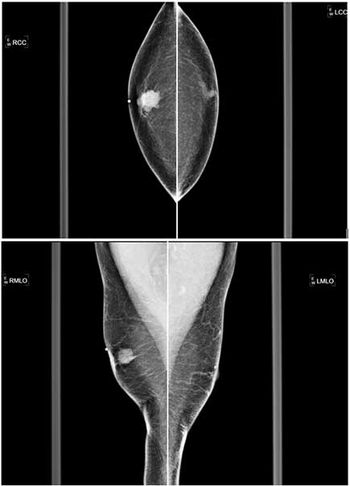

50-year-old male presents with palpable lump on the left breast.